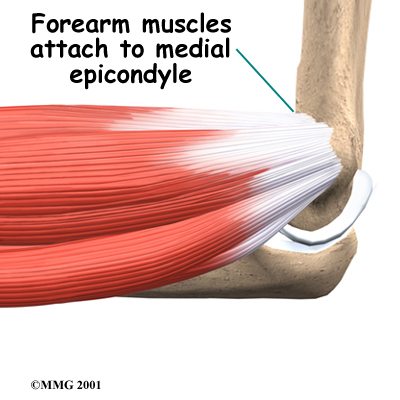

Golfer's elbow causes pain that starts on the inside bump of the elbow, the medial epicondyle. Wrist flexors are the muscles of the forearm that pull the hand forward. The wrist flexors are on the palm side of the forearm. Most of the wrist flexors attach to one main tendon on the medial epicondyle. This tendon is called the common flexor tendon.

The wrist flexor muscles contract when you flex your wrist, twist your forearm down, or grip with your hand. The contracting muscles pull on the flexor tendon. The forces that pull on the tendon can build when you grip a golf club during a golf swing or do other similar actions.

Overuse of the muscles and tendons of the forearm and elbow are the most common reason people develop golfer's elbow. Repeating some types of activities over and over again can put too much strain on the elbow tendons. These activities are not necessarily high-level sports competition. Shoveling, gardening, and hammering nails can all cause the pain of golfer's elbow. Swimmers who try to pick up speed by powering their arm through the water can also strain the flexor tendon at the elbow.